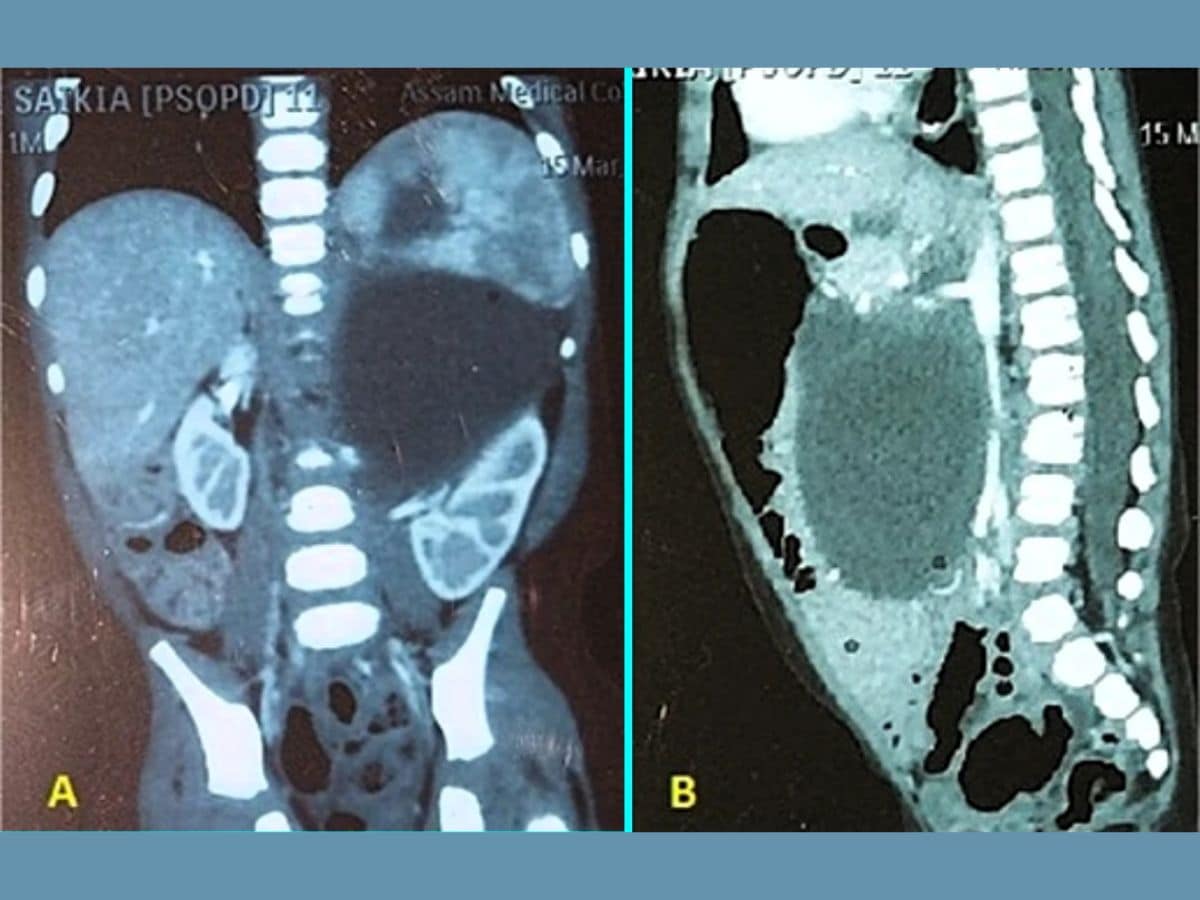

A contrast CT scan finally revealed the cause: a massive growth in the lower abdomen that had displaced vital organs such as the kidneys and pancreas. The findings stunned the medical team.

Further investigation confirmed the condition as neuroglial heterotopia, an extremely rare disorder in which brain tissue develops outside the cranial cavity. While such tissue is occasionally found near the head or neck, its presence deep within the abdomen is extraordinarily rare. Worldwide, only six similar cases have ever been documented.

Given the seriousness of the condition, doctors decided to operate immediately. The surgery was exceptionally challenging, as the mass was located dangerously close to major blood vessels and the kidneys. Once removed, the growth weighed around 550 grams, nearly half a kilogram, an astonishing burden for an infant.